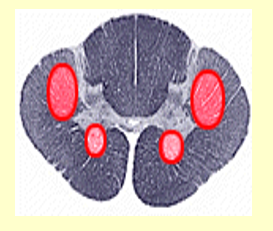

Poliomyelitis